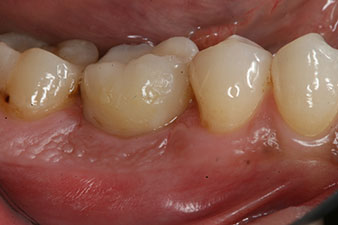

After healing of the soft tissue, the implant stability was measured again before delivery of the prosthetic restoration.

Both values were virtually unchanged and were between the medium and the high range – where the lower value is always used as the reference value that determines the treatment.

Therefore, successful osseointegration and adequate biological stability could be recorded, which enabled an impression to be taken in the same session.

The final pictures show the screw-retained monolithic composite crown in place and the x-ray check (Fig. 9 and 10) (6).